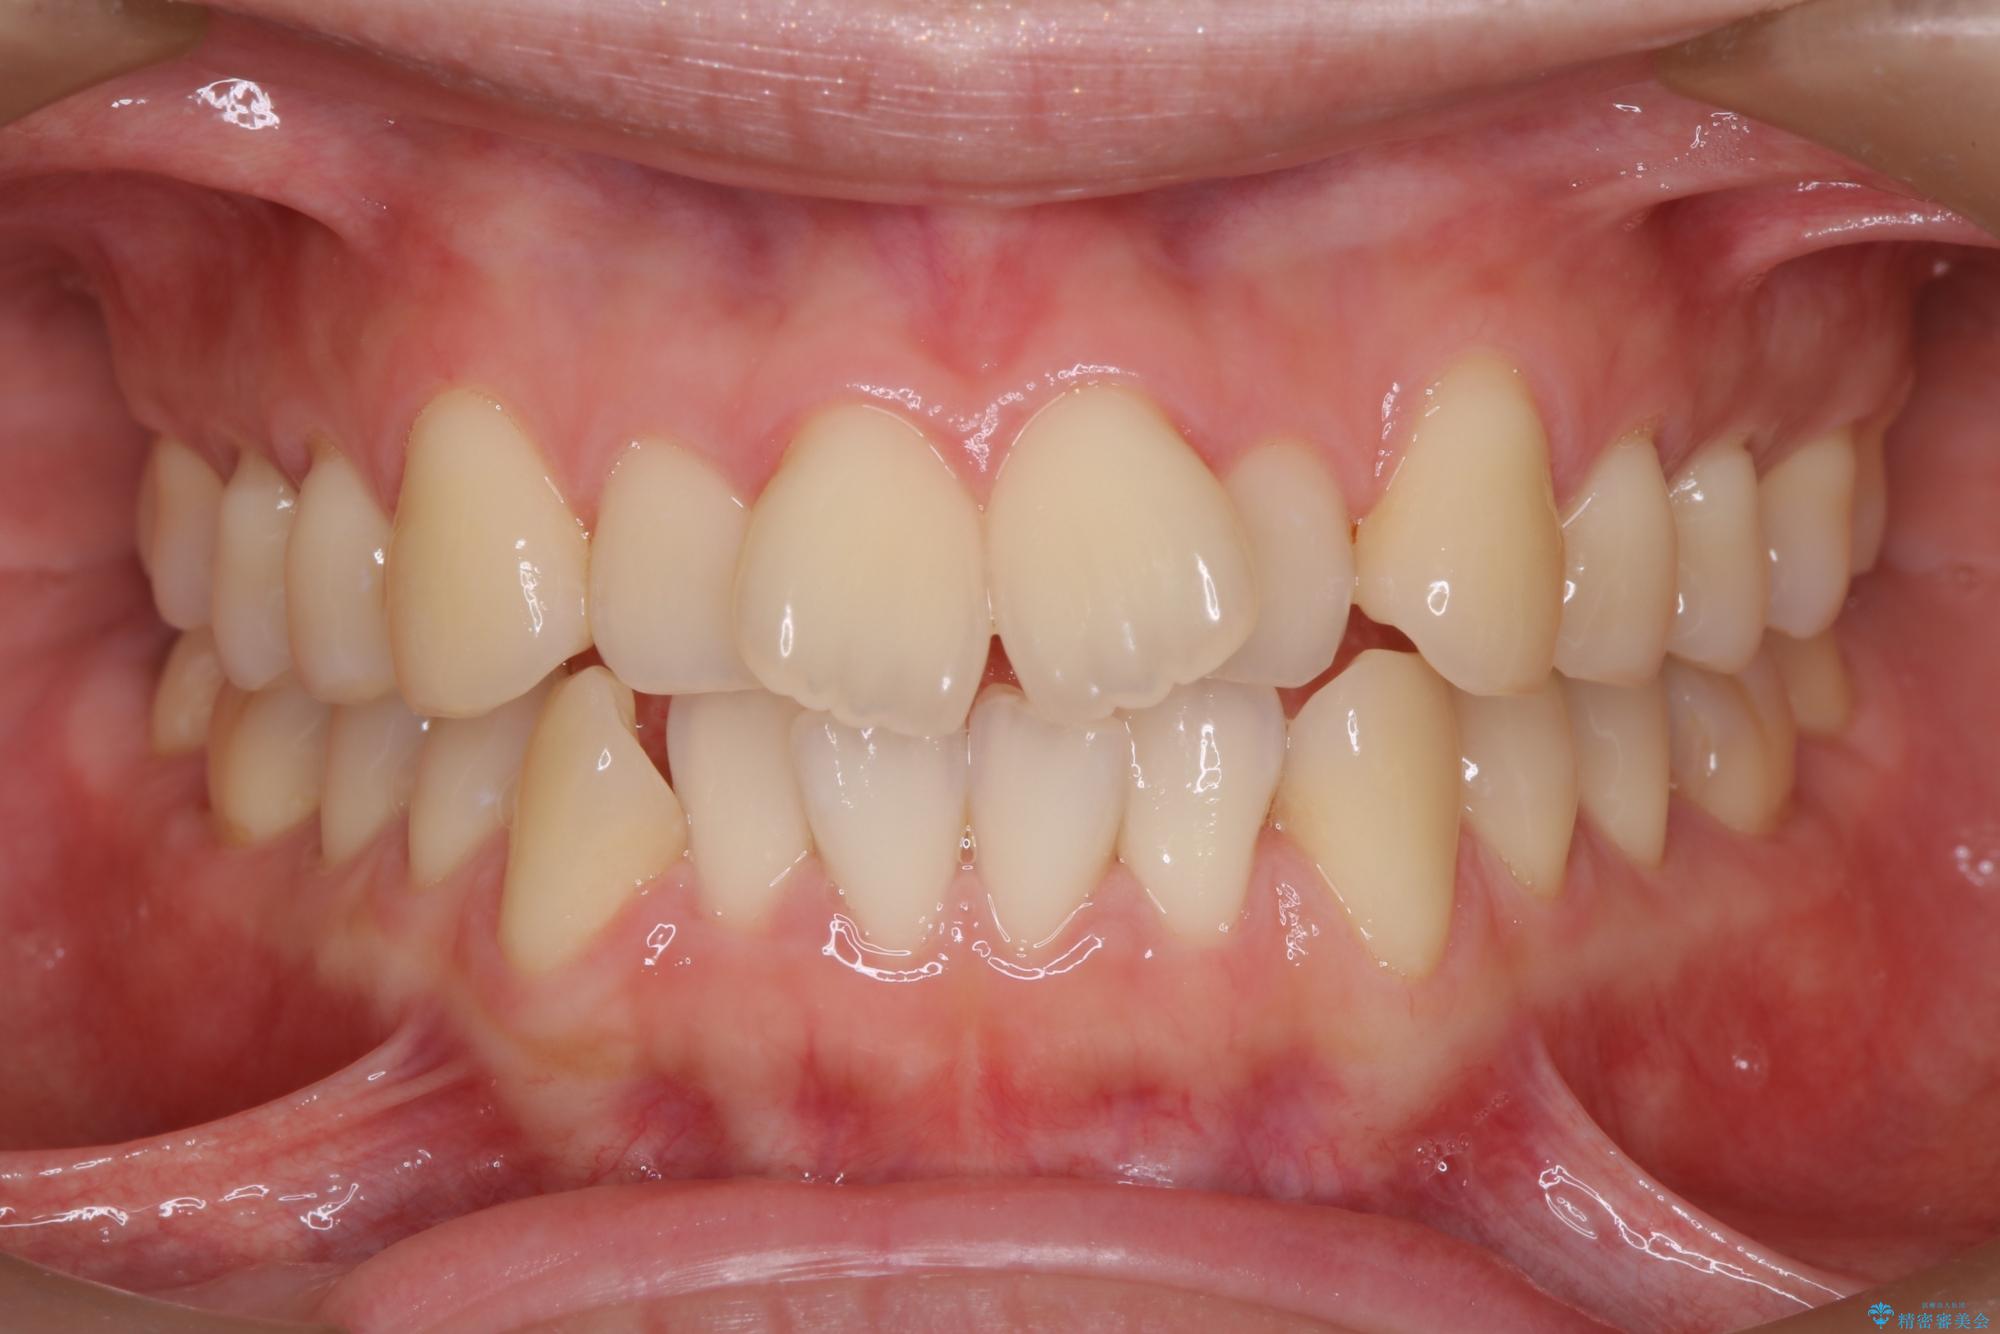

前歯のデコボコが改善され、噛みあわせも綺麗になりました。

歯肉退縮もなく、予定通りに治療を終えることができ大変ご満足いただけました。